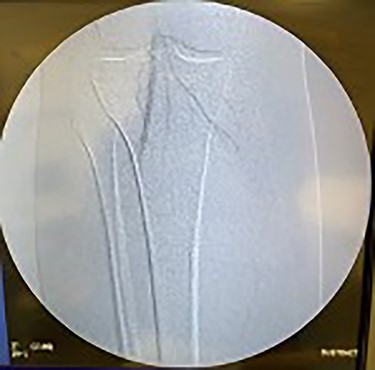

Catheter arteriogram results showed significant occlusion of the left iliac artery (Figs 3 and 4), the right iliac artery (Fig. 1), as well as the distal abdominal aorta (Fig. 2). There were numerous collateral vessels noted, indicating the presence of long-standing proximal stenosis (Fig. 1). The decision was made to use angioplasty to help widen the areas of stenosis. An 8 mm × 40 mm Passeo balloon was advanced from the right femoral artery into the left iliac artery (Fig. 7) and insufflated to 6 mmHg (Fig. 6). The balloon was allowed to remain expanded for 1 min and then was deflated. Next, the distal aorta was repaired in a similar fashion. The balloon was advanced into the distal aorta from the right femoral access and insufflated to 12 mmHg (Fig. 8). The balloon was allowed to remain expanded for 90 s.

Fluoroscopy of bilateral iliac arteries showing significant arterial disease.